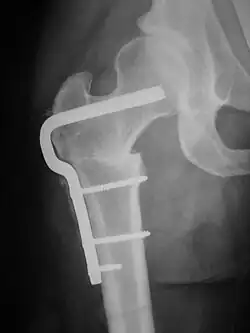

A femoral derotation osteotomy can be performed to correct version abnormalities such as excessive anteversion or retroversion of the hip joint. Excessive anteversion of the femur results in anterior instability of the hip joint while excessive retroversion results in femoroacetabular hip impingement.[5]

A subtrochanteric blade plate or an intramedullary rod can be used to stabilize the osteotomy site in a femoral derotation osteotomy until compete bone healing is achieved; an approach employing an intramedullary rod is much less invasive than one using a subtrochanteric blade plate.}